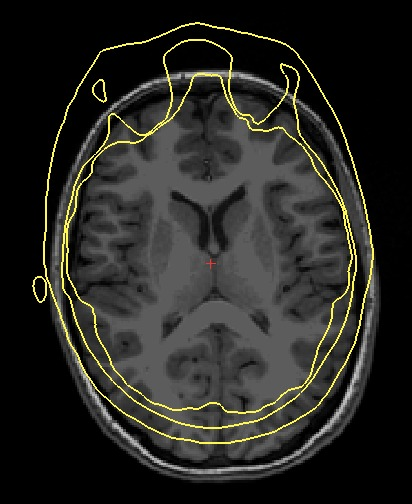

Indeed for some subjects in my dataset (see attached 1) I got the following error when I am going to run make_bem_model.

RuntimeError: Surface inner skull is not completely inside surface outer skull

Oh, that's funny, I got the EXACT same issue than the one we can see on the first figure of this issue! We see the inner surface (yellow) making an excursion out of the two other surfaces at the surface where the MRI is cut (toward the throat). That was the case for almost all my MRI. So I wrote a snippet of code to correct exactly that. It is a fairly specifically tailored piece of code because generalizing it for all possible orientations, convex/concave sections and all possible unexpected cases seemed like a real pain. But it does the job well for this specific case...